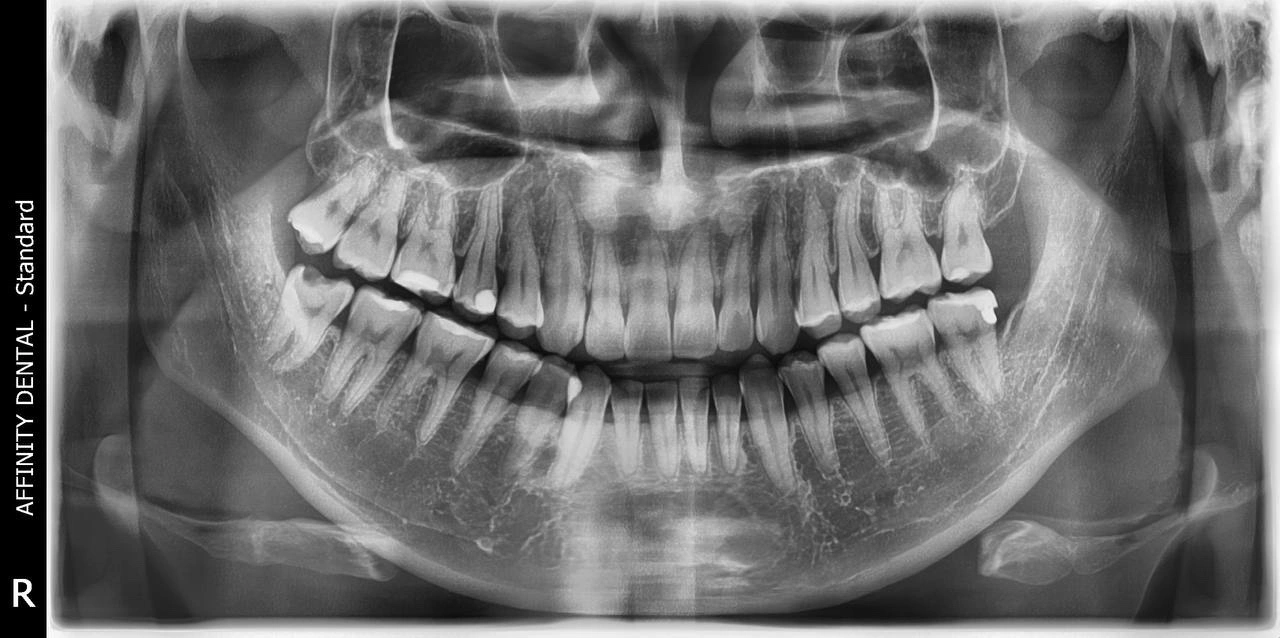

Panoramic dental X-ray showing full mouth view of teeth, jaw, and surrounding structures

A panoramic dental X-ray used for evaluating the entire mouth, including wisdom teeth, jawbones, and dental alignment

A panoramic X-ray (also called a panoramic radiograph or “pano”) is a special type of dental imaging that captures the entire mouth in a single image—including all the teeth in both upper and lower jaws, the jawbones, sinuses, temporomandibular joints (TMJs), and surrounding tissues.

Unlike traditional dental X-rays that focus on small areas, panoramic X-rays offer a broad overview of the mouth. They are extraoral, meaning the machine moves around your head and no sensors need to be placed inside the mouth—making it extremely comfortable even for patients who have a strong gag reflex or dental anxiety.